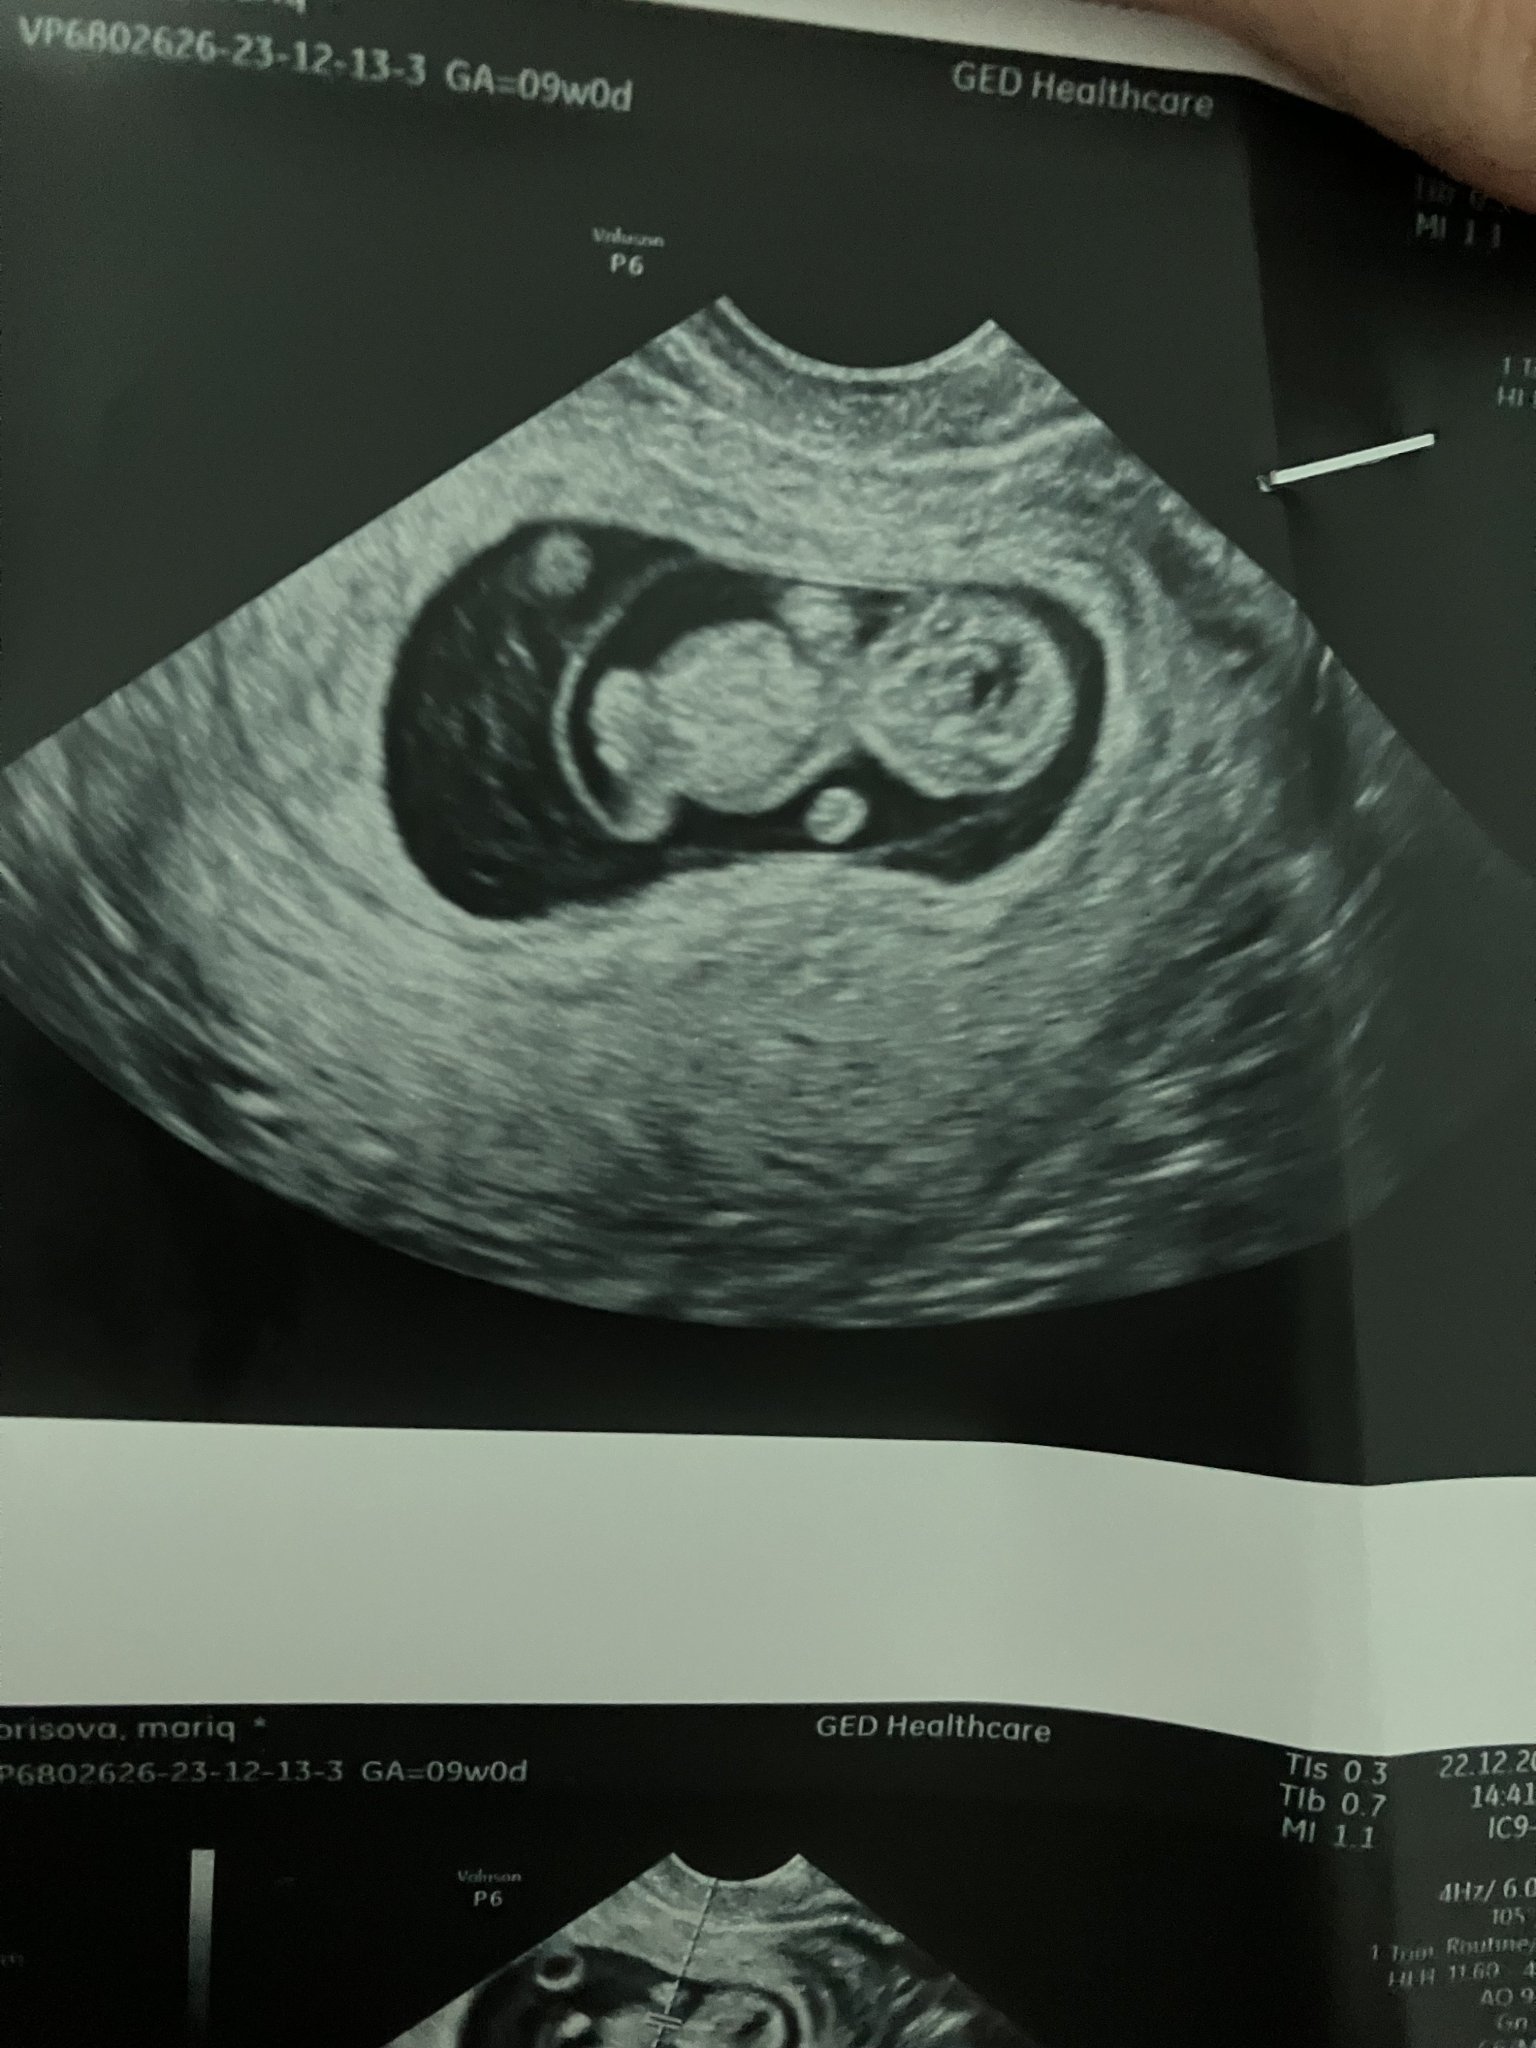

Здравейте. Днес бях на преглед и видях че има нещо някой знае ли какво е? Трябва ли да се притеснявам лекарката не каза нищо може и да не е видяла в 10г.с съм.

Нещо... Има си бебенце, това му е жълтъчното мехурче, нормално е да е там. Пийте си лекарствата и по-спокойно.